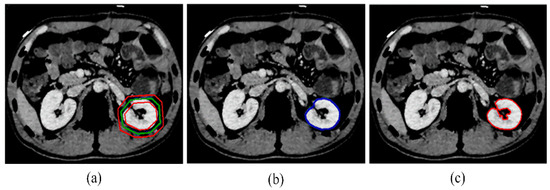

Kidney segmentation from abdominal computed tomography (CT) images is essential for computer-aided kidney diagnosis, pathology detection, and surgical planning. This paper introduces a kidney segmentation method for clinical contrast-enhanced CT images. First, it begins with shape-based preprocessing to remove the spine and ribs. [...] Read more.

Kidney segmentation from abdominal computed tomography (CT) images is essential for computer-aided kidney diagnosis, pathology detection, and surgical planning. This paper introduces a kidney segmentation method for clinical contrast-enhanced CT images. First, it begins with shape-based preprocessing to remove the spine and ribs. Second, a novel clustering algorithm and an initial kidney selection strategy are utilized to locate the initial slices and contours. Finally, an adaptive narrow-band approach based on active contours is developed, followed by a clustering postprocessing to address issues with concave parts. Experimental results demonstrate the high segmentation performance of the proposed method, achieving a Dice Similarity Coefficient of 97.4 ± 1.0% and an Average Symmetric Surface Distance of 0.5 ± 0.2 mm across twenty sequences. Notably, this method eliminates the need for manually setting initial contours and can handle intensity inhomogeneity and varying kidney shapes without extensive training or statistical modeling. Full article